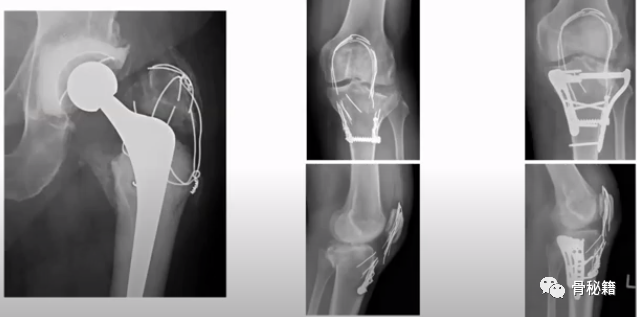

4、大粗隆骨折

8、高段位假体周围骨折,如何捆钢板?

以下是几种不同的缠绕钢板的方法